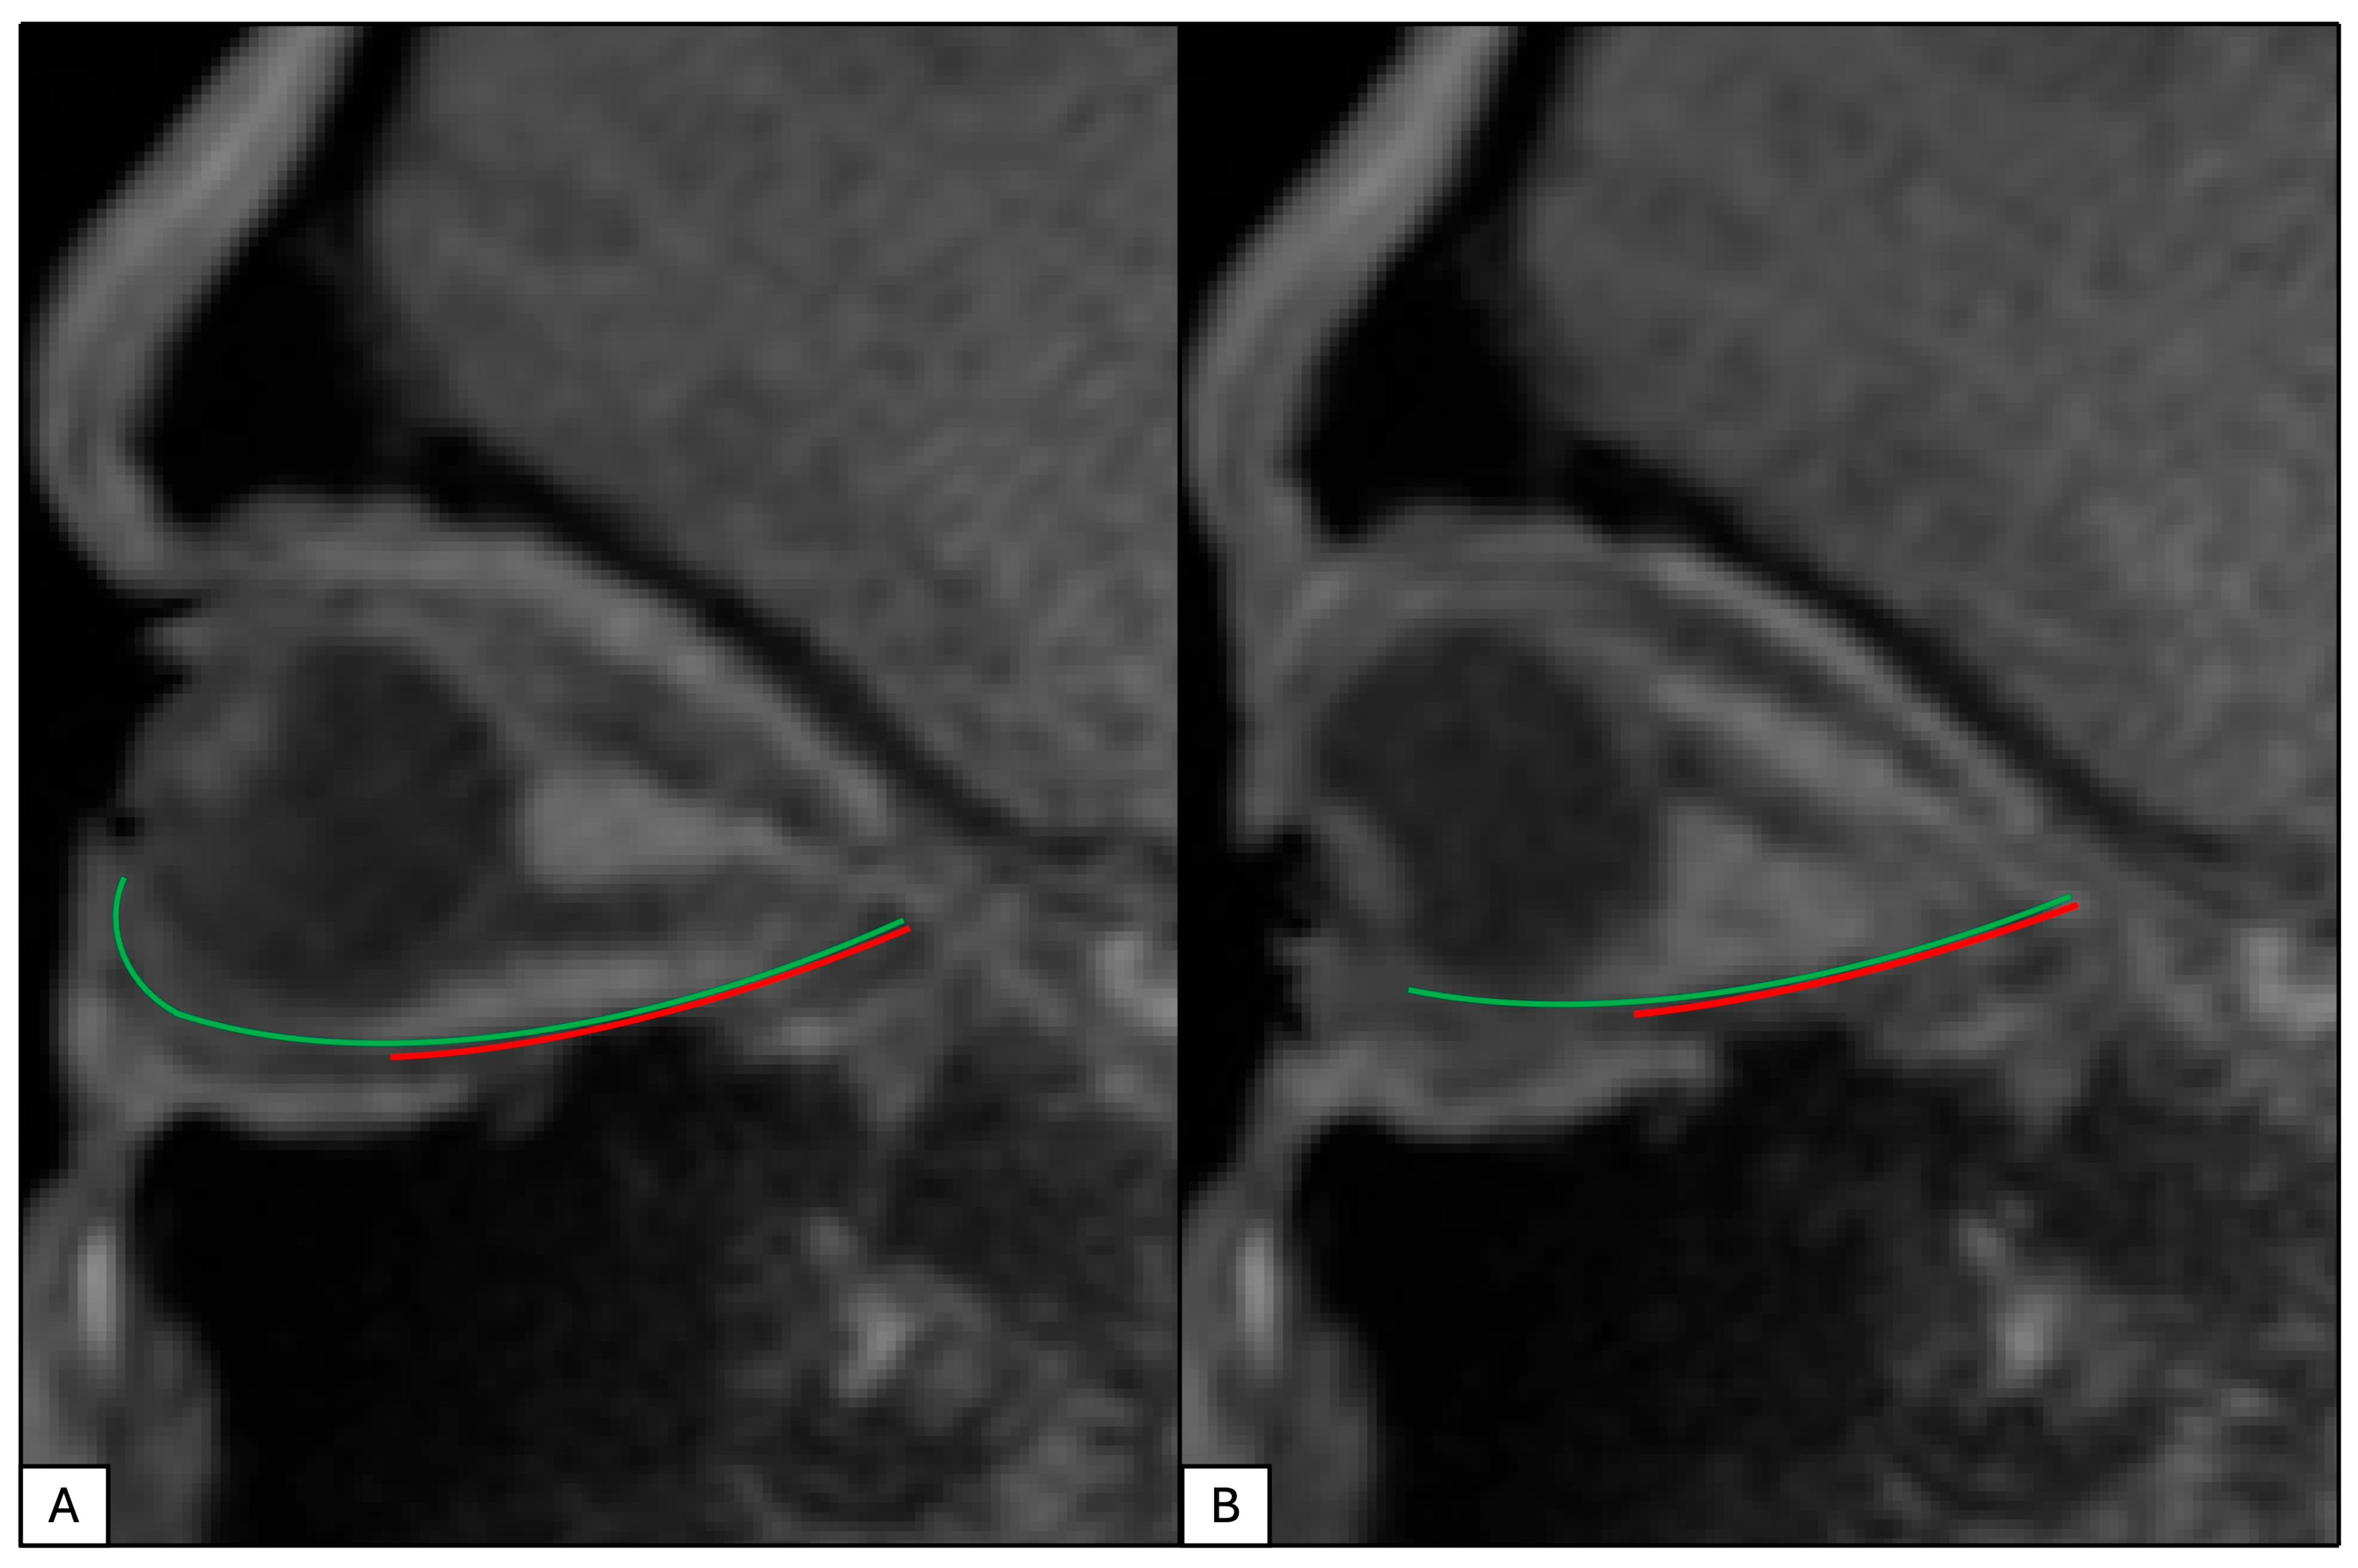

Image analysis was performed on a Macbook Pro (Cupertino, CA, USA) 14-inch Hi-DPI 3024 × 1964 pixel display using the ImageJ graphical user interface version 1.53t, which is publicly available from the National Institutes of Health (Bethesda, MD, USA). Only images free of artifacts and degradation were used for quantitative analysis. Measurements were considered certain to one tenth of a millimeter. The inferior rectus (IR) muscle of each subject was measured from its origin at the orbital apex to insertion in the most extreme up and downgaze. The origin of the IR was approximated by marking the point at which the superior rectus, inferior rectus, and optic nerve appear to converge, the annulus of Zinn (Figure 2). The IR tendon insertion site on the globe was estimated by measuring approximately 6.5 mm inferior to the location of the inferior corneal limbus, the approximate point at which the IR tendon inserts according to the spiral of Tillaux. The insertion points of the rectus muscles certainly vary between individuals, but no study has convincingly asserted any specific relationship between an easily ascertained value (such as axial length) and insertion distance. The most minor susceptibility artifact can obscure the insertion point, making its measurement only certain to the 1.0 mm, rather than 0.1 mm as is required for this study. Therefore, the location defined by the clinically applicable spiral of Tillaux was considered the most exact and repeatable method to determine the insertion point for the inferior rectus muscle. The distance from the origin to the inflection point of the IR (a point where the connective tissue pulley system inflects the muscle path away from its anatomical origin at the annulus of Zinn) was also measured in the most extreme up- and downgazes (Figure 2) [6]. Additionally, the axial length of the globe was measured in the neutral gaze from the anterior cornea to the inner edge of the retina.

For each subject and eye, we computed: (i) the ratio of IR length in the most extreme upgaze to downgaze (UDR) and (ii) the ratio of IR length to the origin inflection point distance (LIR) separately in extreme up and downgazes (Figure 2). All ratios were log-transformed prior to analysis to stabilize variance and allow interpretation of effects as multiplicative changes on the ratio scale.

Figure 2. Illustration of inferior rectus length measurement. Inferior rectus muscle origin to insertion (green) and inflection point (red) in (A) upgaze and (B) downgaze.